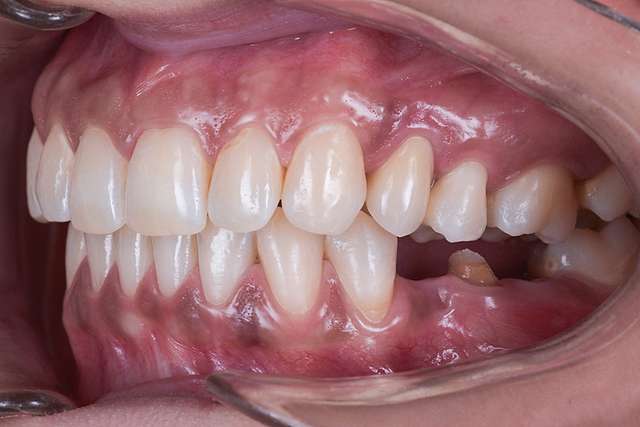

Chirurgia ghidata, ne faciliteaza o pozitie ideal pre-planificata, care nu tine cont doar de os, ci si de o pozitie optima in relatie cu viitorul dinte.Chirurgia ghidata înseamnă o precizie crescuta, care inseamna siguranta mai mare, timp operator mai scazut, si trauma mai mica. De asemenea focusul in acest tip de interventii a migrat spre reconstructia tesuturilor, care e pe termen lung are un impact mult mai mare atat estetic cat si biologic, inserarea implantului in sine fiind trivializata de folosirea ghidului chirurgical. Cazul de fata este un exemplu al acestui tip de abordare.